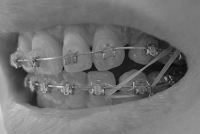

エラスティックゴムがパワーアップしました

今回のは直径4ミリ。

掛け方も前回とは逆で、下の歯を奥に引っ張ることが目的です。

左側はちょっと変則掛け。い、痛い・・・

ゴムがあんまり伸びへんから、口が開かへんー

これで限界。これ以上は痛くて無理~~~

まぁ、普通にしゃべる分にはこれでもいけるから、今回もゴム掛けがんばろう。